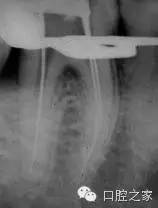

為了能夠直觀的確定額外牙根的存在,需要不同角度的X線投照來顯示。在下頜第一磨牙的根管治療過程中,最初的分角線投照是十分必要的(圖1a)。首先,使用根管銼來定位額外牙根,從表觀上類似穿孔的表現(xiàn)。如果根尖片所示不是非常確定,根尖定位儀能夠提供有效的、可信賴的信息來進(jìn)行鑒別診斷,從而確定額外根管的存在。Walker和Quackenbush 總結(jié)了對咬合翼片的簡單分析可以探查到90%的病例中的遠(yuǎn)中舌根。